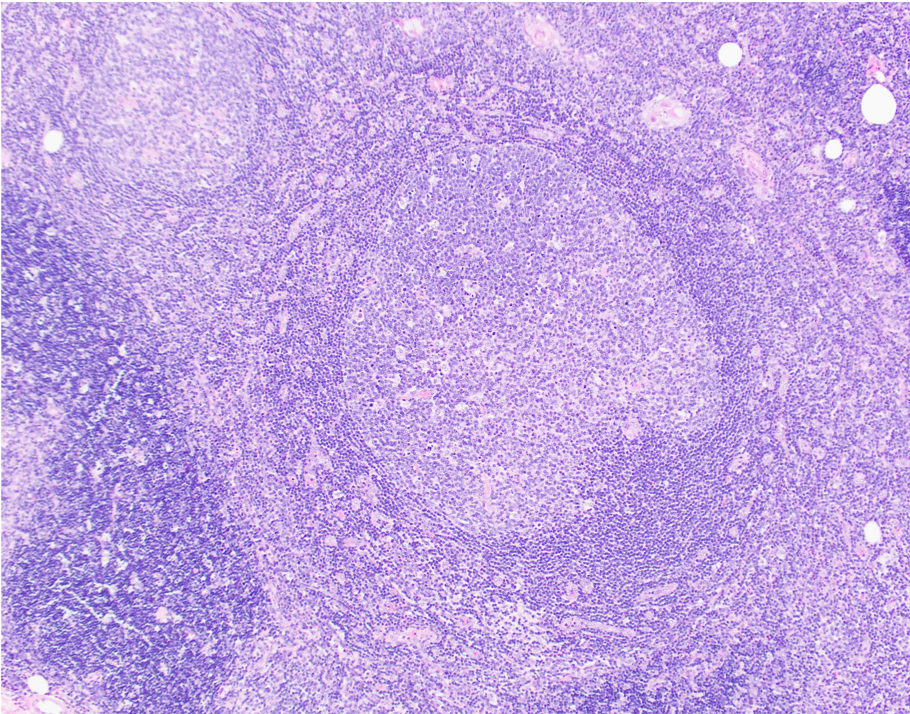

Microscopic (histologic) description

- Preserved thymic architecture

- Increased number of lymphoid follicles with prominent germinal centers of different sizes and tingible body macrophages (StatPearls: Thymic Hyperplasia [Accessed 28 February 2023], Histopathology 2009;54:69)

- Frequent Hassall corpuscles

- Rare germinal centers may be seen in the normal thymus, no clear cutoff is defined

Microscopic (histologic) images